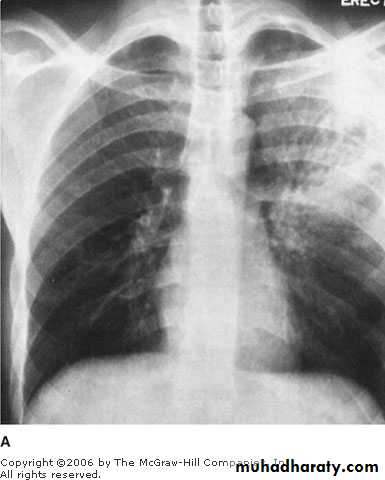

A 37 years old presented with chronic cough, fever and hemoptysis.He gave history of chronic steroid use for his poorly controlled asthma.

His chest X ray shown.

What is the most likely Dx?